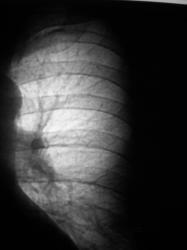

Провели рентгенографию в прямой стандартной проекции. С учетом "неубедительности" теневой картины "решили понаблюдать".

Зафиксировано увеличение тени в размерах. Произведена рентгенография в прямой стандартной проекции.

Было высказано предположение о наличии "маленького периферического рака", зафиксирована "линзеподобная тень" паракостально. Пациент направлен на консультацию в онкологический диспансер.